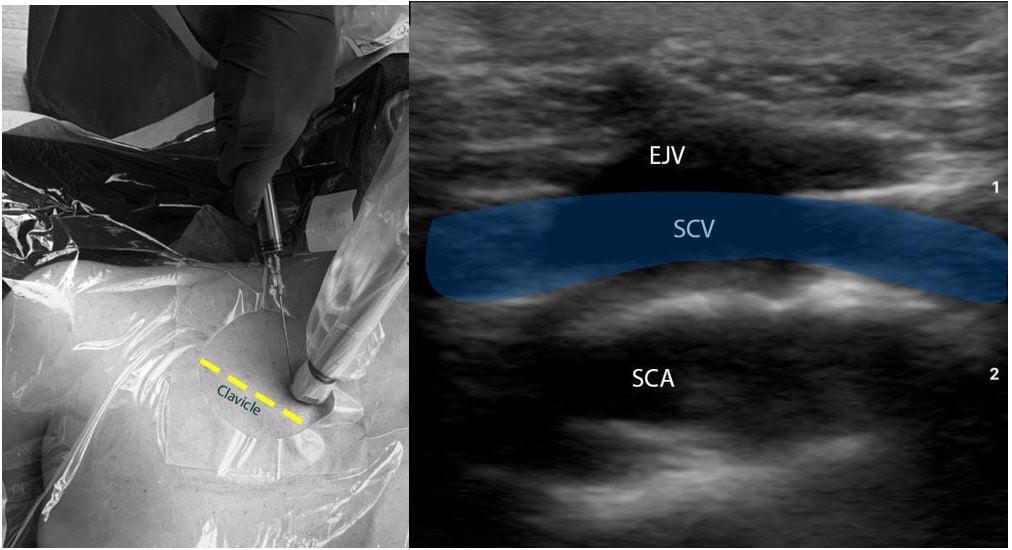

B. Supraclavicular in-plane approach (Figure 3):

- Position the patient in the Trendelenburg position to allow venous engorgement and minimize the risk of air embolism. The patient should be prepped and draped in the usual sterile fashion. The ipsilateral IJV should also be prepped and draped.

- Place the transducer in the supraclavicular fossa abutting the ipsilateral clavicle. Angle the probe anteriorly to visualize the supraclavicular SCV. Slide the probe medially along the linear course of SCV until it’s confluence with the IJV is visualized.

- Evaluate the depth, caliber, and patency of the SCV and IJV. Use compressibility and/or pulse-wave Doppler to confirm that the structure visualized is indeed the vein, and not the artery.

- Insert the needle in the in-plane approach. The needle should be advanced slowly under direct visualization. The lung pleura lies underneath the vessel and must be approached with caution.

- If needle visualization is lost, it is important to stop advancing the needle. Withdraw slightly and re-visualize the needle before proceeding.

- Once within the lumen of the vessel, insert the guidewire and monitor the guidewire placement in real time with ultrasound. The guidewire location in right atrium/ventricle can also be rapidly confirmed by a subxiphoid view of the heart.

- Make a small incision on the skin, dilate the vessel, and insert the catheter over the guidewire.

Figure 3: Ultrasound-guided subclavian vein cannulation. EJV (External Jugular Vein), SCV (subclavian vein), SCA (subclavian artery).